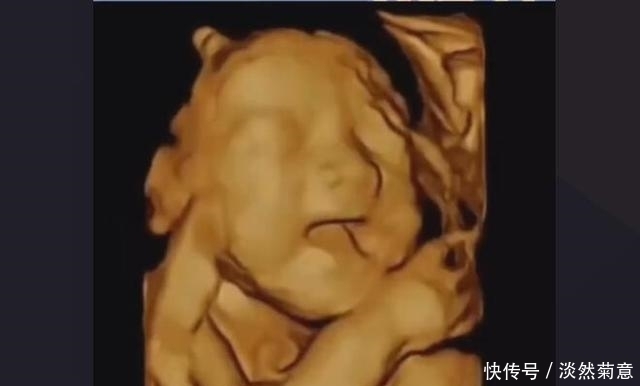

③ 孕20-24周的产检:

这个阶段 有两项重要的检查,一项是排畸B超,现在多是直接做四维排畸,另一项是葡萄糖耐量实验,看孕妈血糖是否存在异常,可能会安排在孕24周一起做,具体听医生的安排就好。